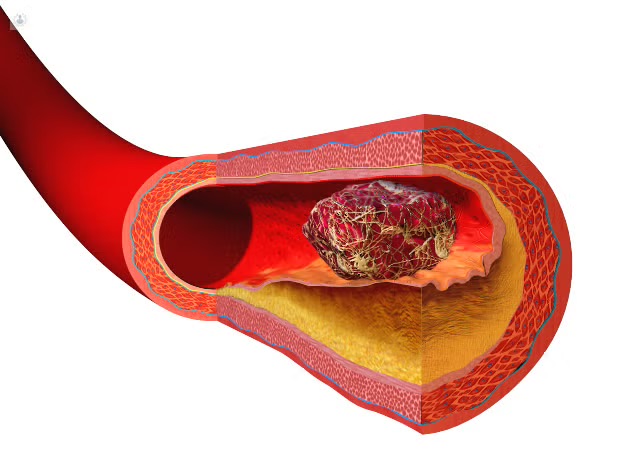

Las várices son venas dilatadas y tortuosas que aparecen principalmente en las piernas debido a una alteración en la circulación sanguínea. No solo representan un problema estético, sino que también pueden provocar dolor, cansancio, hinchazón y complicaciones venosas si no se tratan a tiempo.